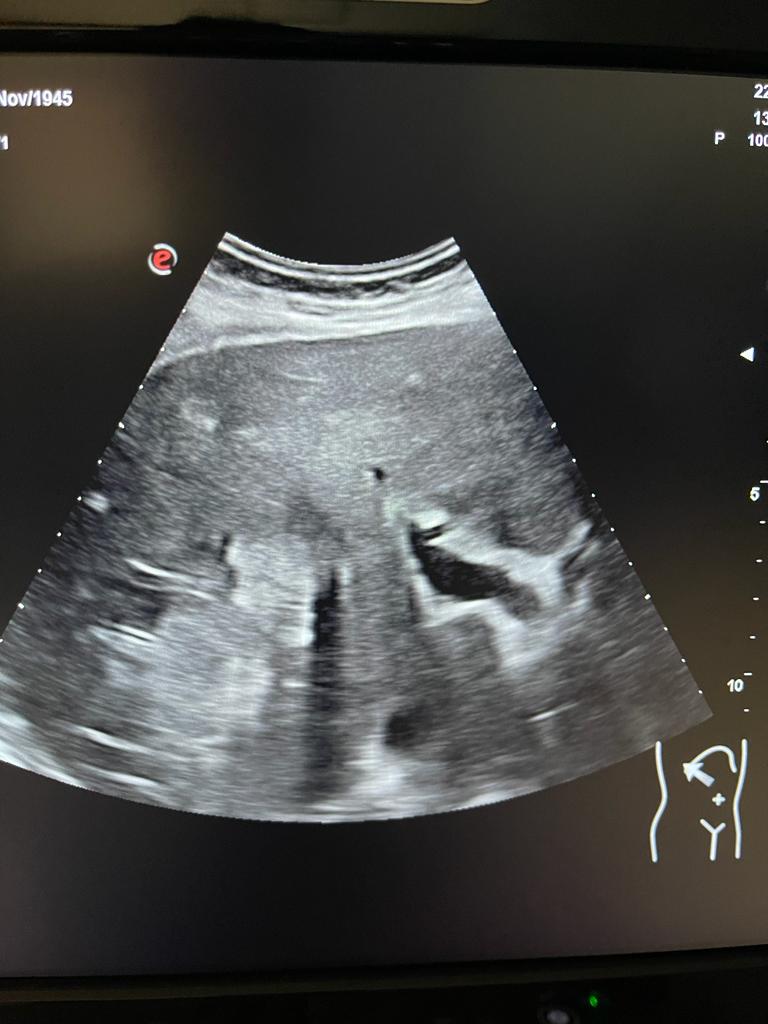

Se aprecia hígado heterogéneo con múltiples LOES hepáticas hiperecogénicas (una de ellas de unos 7x7 cm), sin captación de doppler. Al menos otras 2 LOES de menor tamaño presentan halo hipoecoico. Vesícula replecionada de contornos lisos y sin litiasis en su interior. Ambos riñones visualizados de tamaño normal y sin datos de hidronefrosis.

Se decide pedir ecografía reglada para valorar estudio posterior. Ecografía confirma sospecha de LOES intrahepáticas. Desde radiología amplian estudio con TAC: lesión ósea lítica con criterios de agresividad expansiva con masa de partes blandas en vertiente posterior de pala ilíaca izquierda.